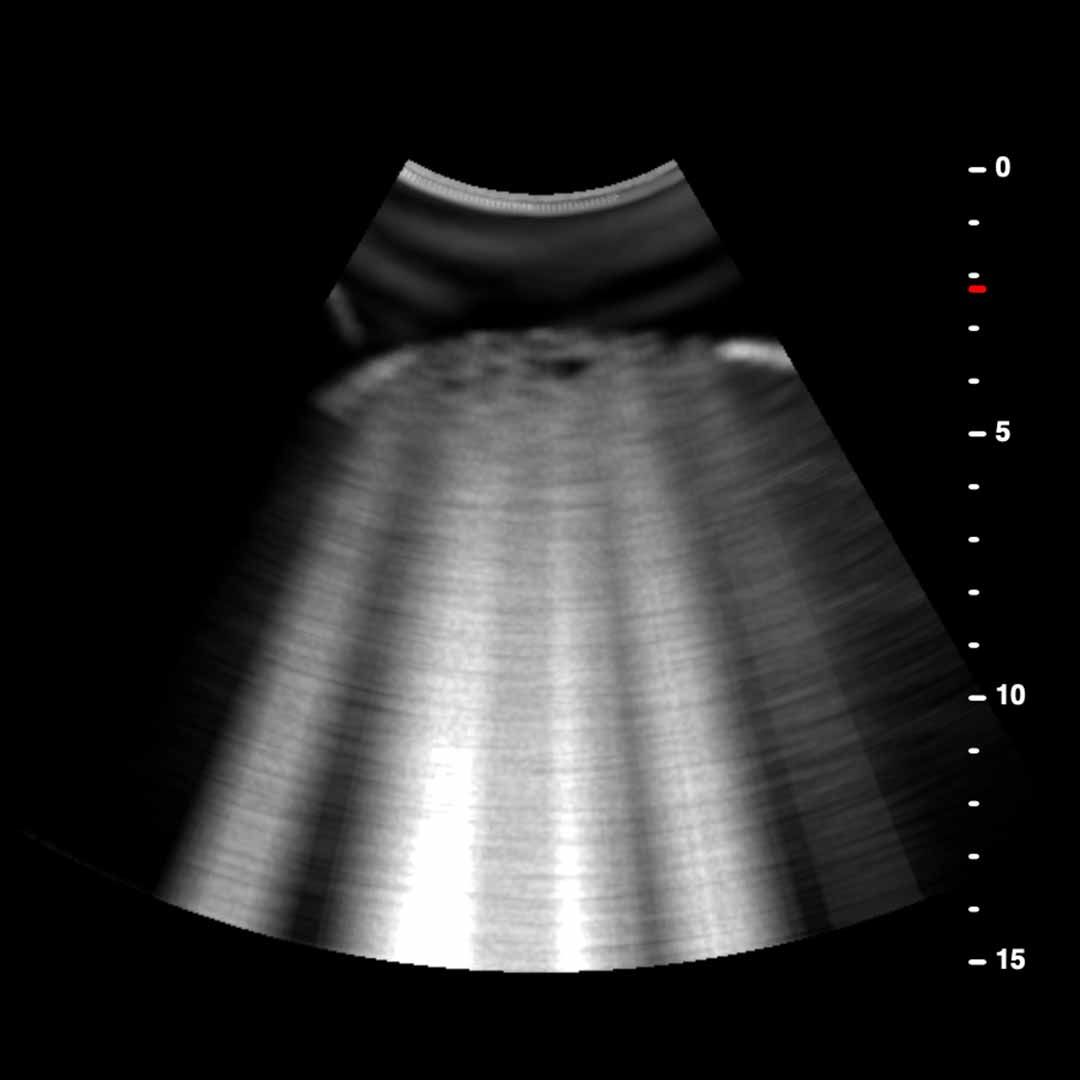

From pocus.sg

B Lines Point of Care Ultrasound S Lines Ultrasound Information concerning lines, signs, and lung profiles in this review is based mainly on d. Lichtenstein’s research and book “whole body ultrasound in. In early pneumonia fluid fills only some of the alveoli. It is imperative to be familiar with ultrasound physics, normal lung. On lus, the parietal pleura (outer pleural layer attached to the chest wall) and visceral pleura. S Lines Ultrasound.